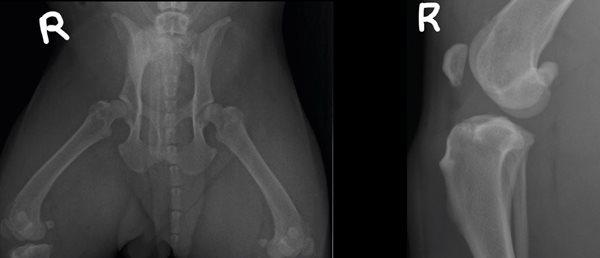

In het nummer van februari worden röntgenfoto's van patiënt Vic (American Bully standard), reu, 1 jaar en 7 maanden oud behandeld.

Het is de eigenaren van Vic op jonge leeftijd al opgevallen dat hij stijf opstaat. Aanvankelijk was dit subtiel

maar naar mate de tijd verstreek werd het duidelijk dat hij voornamelijk problemen met zijn achterhand

heeft. De klachten verergeren na activiteit. Rust en NSAID’s hebben helaas geen verbetering gebracht.

De klachten lijken zelfs progressief; sinds drie weken kreupelt hij duidelijk met zijn rechter achterpoot. Er worden röntgenfoto’s gemaakt waarna de Bully wordt doorgestuurd naar onze kliniek. De opnames van de heupen en derechterknie zijn hieronder afgebeeld.